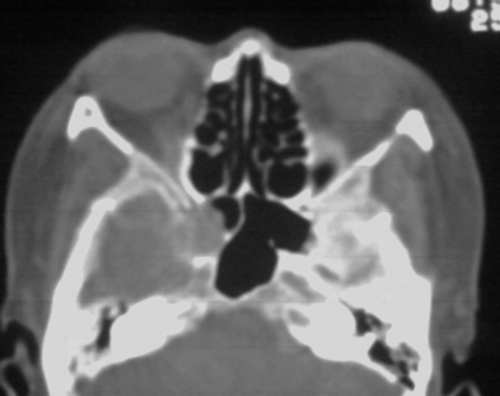

以下是引用随光逐影在2008-3-28 11:41:00的发言:[br]右侧蝶骨大翼骨质破坏,骨质破坏区内为软组织密度影填塞,右侧翼腭窝似有扩大,右侧乳突部分蜂房密度增高;疑鼻咽部肿瘤。建议:行鼻咽部ct扫描检查。另:右侧上颌窦黏膜下囊肿(或息肉)。

以下是引用jiangjing在2008-3-28 14:09:00的发言:[br]右侧蝶骨大翼骨质破坏,骨质破坏区内为软组织密度影填塞,右侧翼腭窝似有扩大,右侧乳突部分蜂房密度增高;疑鼻咽部肿瘤。建议:行鼻咽部ct扫描检查。另:右侧上颌窦黏膜下囊肿(或息肉)。